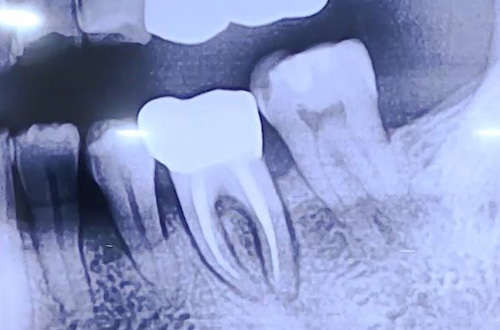

AFTER

치료 유형 어금니 즉시 임플란트

발치한 자리에 임플란트를 식립하고 빈 공간을 뼈이식으로 채워드렸고,

임플란트가 단단히 굳고 나면 보철을 완성해 마무리할 계획입니다.